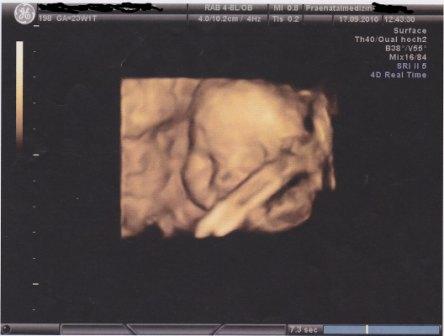

@me bei uns ist alles okay. Gestern war wieder VU. Diesmal ohne US. Kann aber die Begründung vom FA verstehen. Wir waren ja letzten Freitag erneut beim Fein-US und da wurde unser Sohn vermessen. Soviel wird sich in einer Woche auch nicht ändern. Trotzdem ich hätte gern unseren Sohn auf dem US gesehen. Aber der nächste Termin ist schon am 7. Okt. also nicht mal mehr 14 Tage. :juhu: Wobei ich merke ja Sohnemann täglich, schließlich tritt er immer gegen meine Bauchwand. :D

Anbei noch ein 3 D Bild von Junior

Unser Sohn bei 23+1 am 17.09.2010